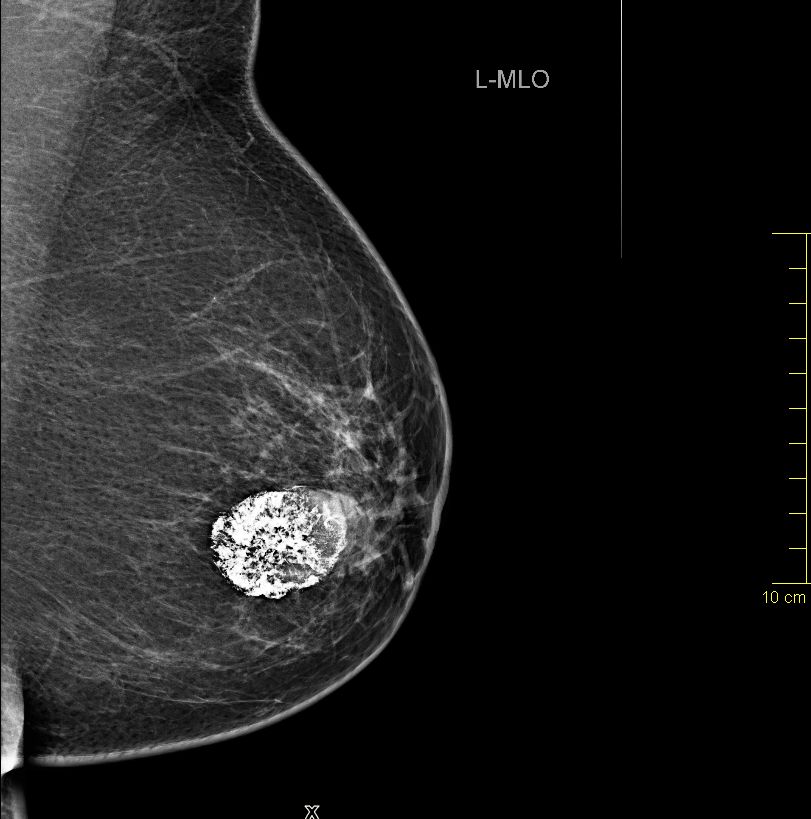

Liegen in einer Brust mehrere Fibroadenome nebeneinander vor, erhöht dies unter anderem das Risiko für bösartige Veränderungen in der Umgebung Wächst das Fibroadenom schnell und über eine Größe von drei Zentimetern hinaus oder planen Sie eine Schwangerschaft, wird Ihr Arzt möglicherweise eine Operation empfehlen. Kalk kommt in der Brust sehr häufig vor, zumeist ist er gutartig und harmlos Dennoch sollten Verkalkungen regelmäßig abgeklärt werden, denn sie können auch Anzeichen von Brustkrebs sein Bei manchen Frauen finden sich bei einer Mammografie Kalkablagerungen auf den Röntgenbildern (Mammogramme). Sie finden uns auch bei Facebook.

Die Bilder machen eventuell vorhandene Mikrokalkablagerungen sichtbar Mikrokalk erscheint in der Mammografie weiß Wenn er verstreut auftritt und zu keiner Struktur in der Brust gehört, ist die Diagnose Brustkrebs sehr wahscheinlich Auch die Verteilung und Größe des Mikrokalks ist aufschlussreich. Ein Tumor ist definiert als eine Schwellung oder krankhafte Ausdehnung der Zelle als Folge ihres Überwachsens und ihrer übermäßigen Teilung Nicht alle Tumore sind jedoch krebsartig (bösartig) Er ist gutartig, wenn die Zellen, die den Tumor bilden, normal sind. 1,407 Followers, 144 Following, 333 Posts See Instagram photos and videos from Football Austria (@footballaustria).

Die Bilder machen eventuell vorhandene Mikrokalkablagerungen sichtbar Mikrokalk erscheint in der Mammografie weiß Wenn er verstreut auftritt und zu keiner Struktur in der Brust gehört, ist die Diagnose Brustkrebs sehr wahscheinlich Auch die Verteilung und Größe des Mikrokalks ist aufschlussreich. Neben der Bestätigung, ob es sich um Krebs oder einen benignen Tumor handelt, geben die Bilder auch Aufschluss über die aktuelle Tumorgröße und mögliche Metastasen im untersuchten Körperbereich. Chondrom gutartiger Tumor aus Knorpel Die schmerzfreie Knochenwulst in der Nähe von Gelenken wird meist nur durch Zufall beim Röntgen entdeckt Chondrome kommen häufig an den Händen, an.